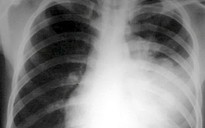

Hiện, viêm phổi và tiêu chảy vẫn là hai nguyên nhân chính gây tử vong ở trẻ dưới 5 tuổi tại Việt Nam. Trong giai đoạn 2016 - 2023, virus rota là nguyên nhân gây ra ca tiêu chảy cấp ở 20% - 50% trẻ nhỏ. Ước tính virus rota khiến hàng trăm nghìn trẻ phải nhập viện và hàng ngàn trẻ phải cấp cứu mỗi năm, đặc biệt ở vùng sâu vùng xa, những địa phương chưa có điều kiện tiếp cận với vắc xin phòng bệnh trong tiêm chủng dịch vụ.

Sau vắc xin rota, năm 2025 có thêm vắc xin phế cầu (phế cầu khuẩn là nguyên nhân rất thường gặp gây viêm phổi, viêm màng não, nhiễm khuẩn huyết ở trẻ em); vắc xin ngừa HPV (HPV là virus gây ung thư cổ tử cung ở nữ và một số bệnh ở nam giới) sẽ đưa vào tiêm chủng mở rộng quốc gia từ 2026.